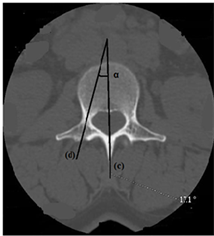

Figure 3. Axial section of the lumbar vertebra L3 passing through the pedicles (dimensions of the pedicle). a: pedicle length; b: width of the pedicle; c: medio-sagittal line passing through the vertebral body, the spinal canal and the spinous process behind; d: sagittal axis of the pedicle passing through its middle; α: angle of inclination of the axis of the pedicle with respect to the sagittal plane.

The length of the pedicle decreased from L1 to L5 and there was no significant difference between the left and the right or between the man and the woman (p = 0.1). Pedicle width increased from L1 to L5 and was the same between left and right. Values in men were significantly higher than in women (p ˂ 0.001). The alpha angle increased from L1 to L5 (Figure 3). There was no significant difference between the left and right or between the man and the woman (p = 0.07). The beta angle (Figure 4) decreased from L1 to L5. The difference between the man and the woman was not statistically significant (p = 0.3).